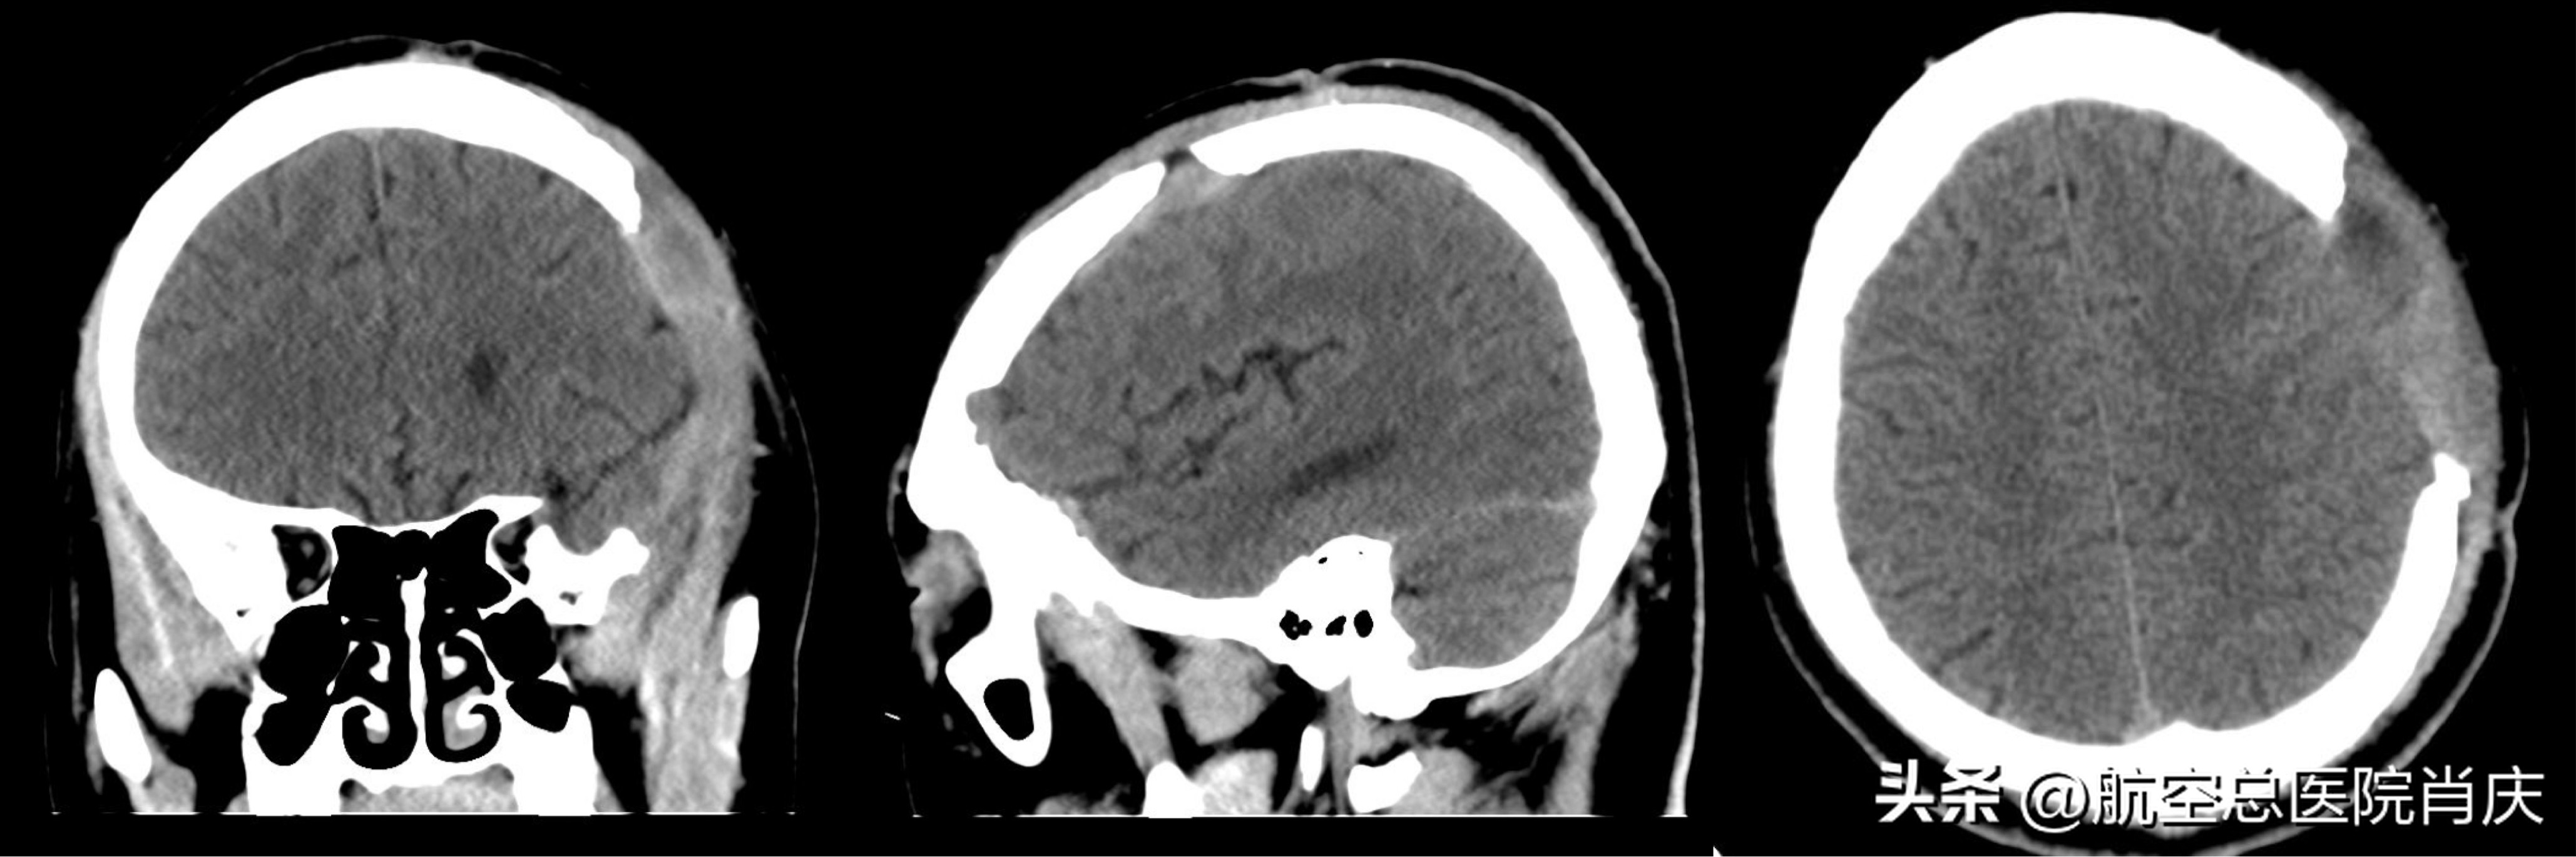

术后

常某脑外伤术后持续高热,病情危急,入院后完善各项检查的同时进行抗感染及保肝治疗。根据头颅影像学检查及患者体征明确诊断,曾开放性颅脑损伤,去骨瓣减压术后,仍存在皮下积液及体温升高,需清除局部脓苔,并结合抗感染治疗。确定了治疗方案,肖主任团队为常某在全麻下行硬膜外脓肿清除术。手术非常顺利成功,术后继续抗感染对症治疗。历时18天的医治,患者常某恢复良好,不再有发热、头痛的症状,可以正常交流,起身,行走,已经可以出院休养。